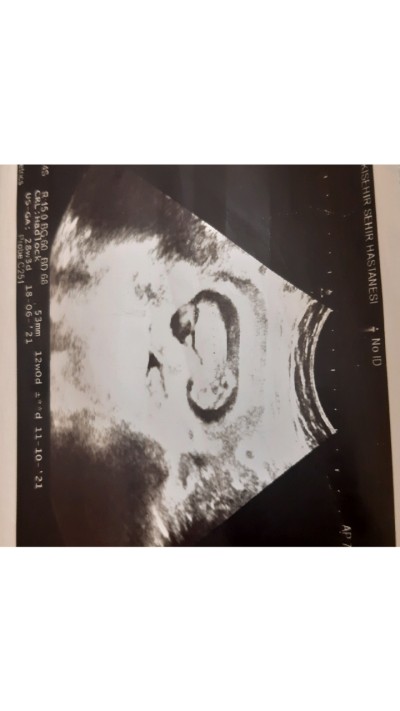

cinsiyet tahmininde bulunabilirmisiniz 12 haftalık bebeğim ilk gebeliğim merak ediyorum

12